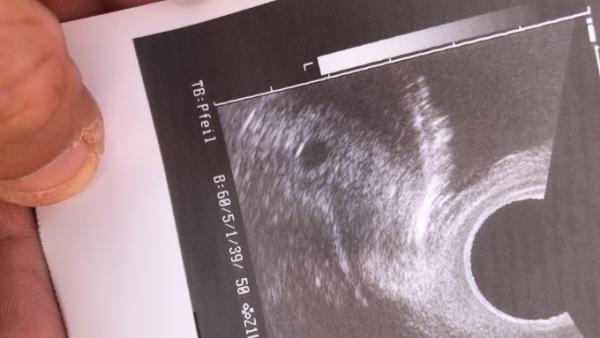

Hallo :) Ich hatte heute auch meinen ersten Termin , bei 5+ 3 nur wegen Arbeitgeber und Kontrolle :) Sieht alles bestens aus und in 4 Wochen soll ich erneut kommen . Alles alles gute morgen für dich :)

Bild zu